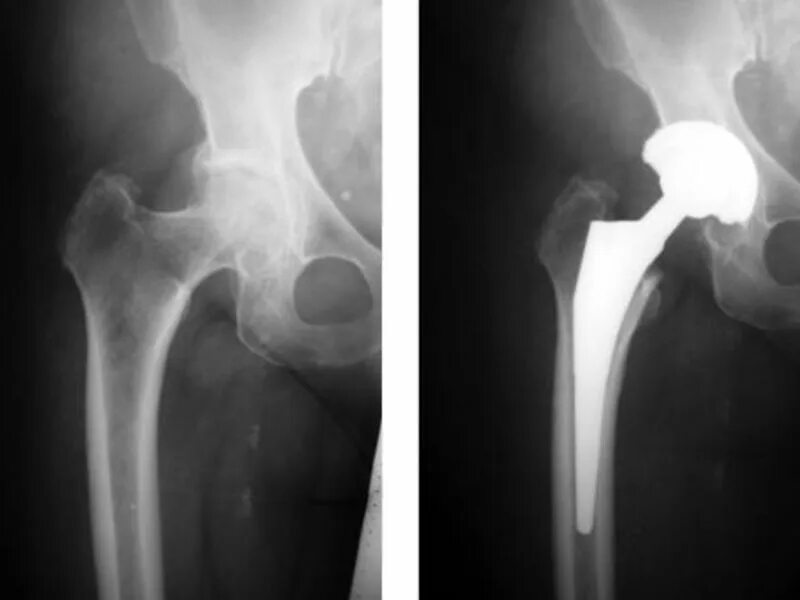

Операция при коксартрозе тазобедренного сустава